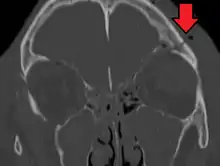

| A subtle temporal bone fracture as seen on CT in a person with a severe head injury | |